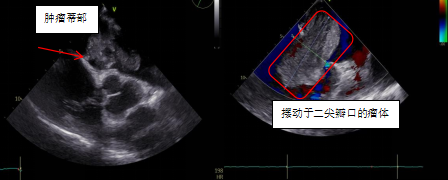

患者郑大爷,因“反复劳累性心累、气促2+月,加重10+天”到我院胸心血管外科就诊。本次病情发作后,郑大爷夜间无法平卧,呈端坐呼吸,伴咳嗽、咳痰,为白色泡沫痰,心悸、心慌明显,并感头晕,测血压偏低,为休克状态(80-90/40-50mmHg)。入院经心脏彩超、胸部影像学等相关检查,发现导致郑大爷症状的元凶:“巨大左心房占位”,支持粘液瘤样改变,同期发现患者伴有卵圆孔未闭、三尖瓣中度关闭不全等心脏问题。

程永波副主任医师介绍到,心房粘液瘤是最常见的原发性心脏肿瘤,心脏各个房室均可发生粘液瘤,位于左心房者最多见。体积很小的粘液瘤可以没有症状,肿瘤长大后导致血流动力学改变,即可出现全身表现和周围血管栓塞等症状。左心房粘液瘤最常见的临床症状是由于房室瓣血流受阻引起心悸、气急等。移动度较大的粘液瘤若突然阻塞房室瓣瓣孔,病人可发作晕厥、抽搐,甚至猝死。粘液瘤病例明确诊断后应尽早施行手术摘除肿瘤,恢复心脏房室正常通道,避免肿瘤发生恶变以及突然堵塞房室瓣瓣口引致猝死,或者因肿瘤碎屑脱落并发全身各部位的栓塞。